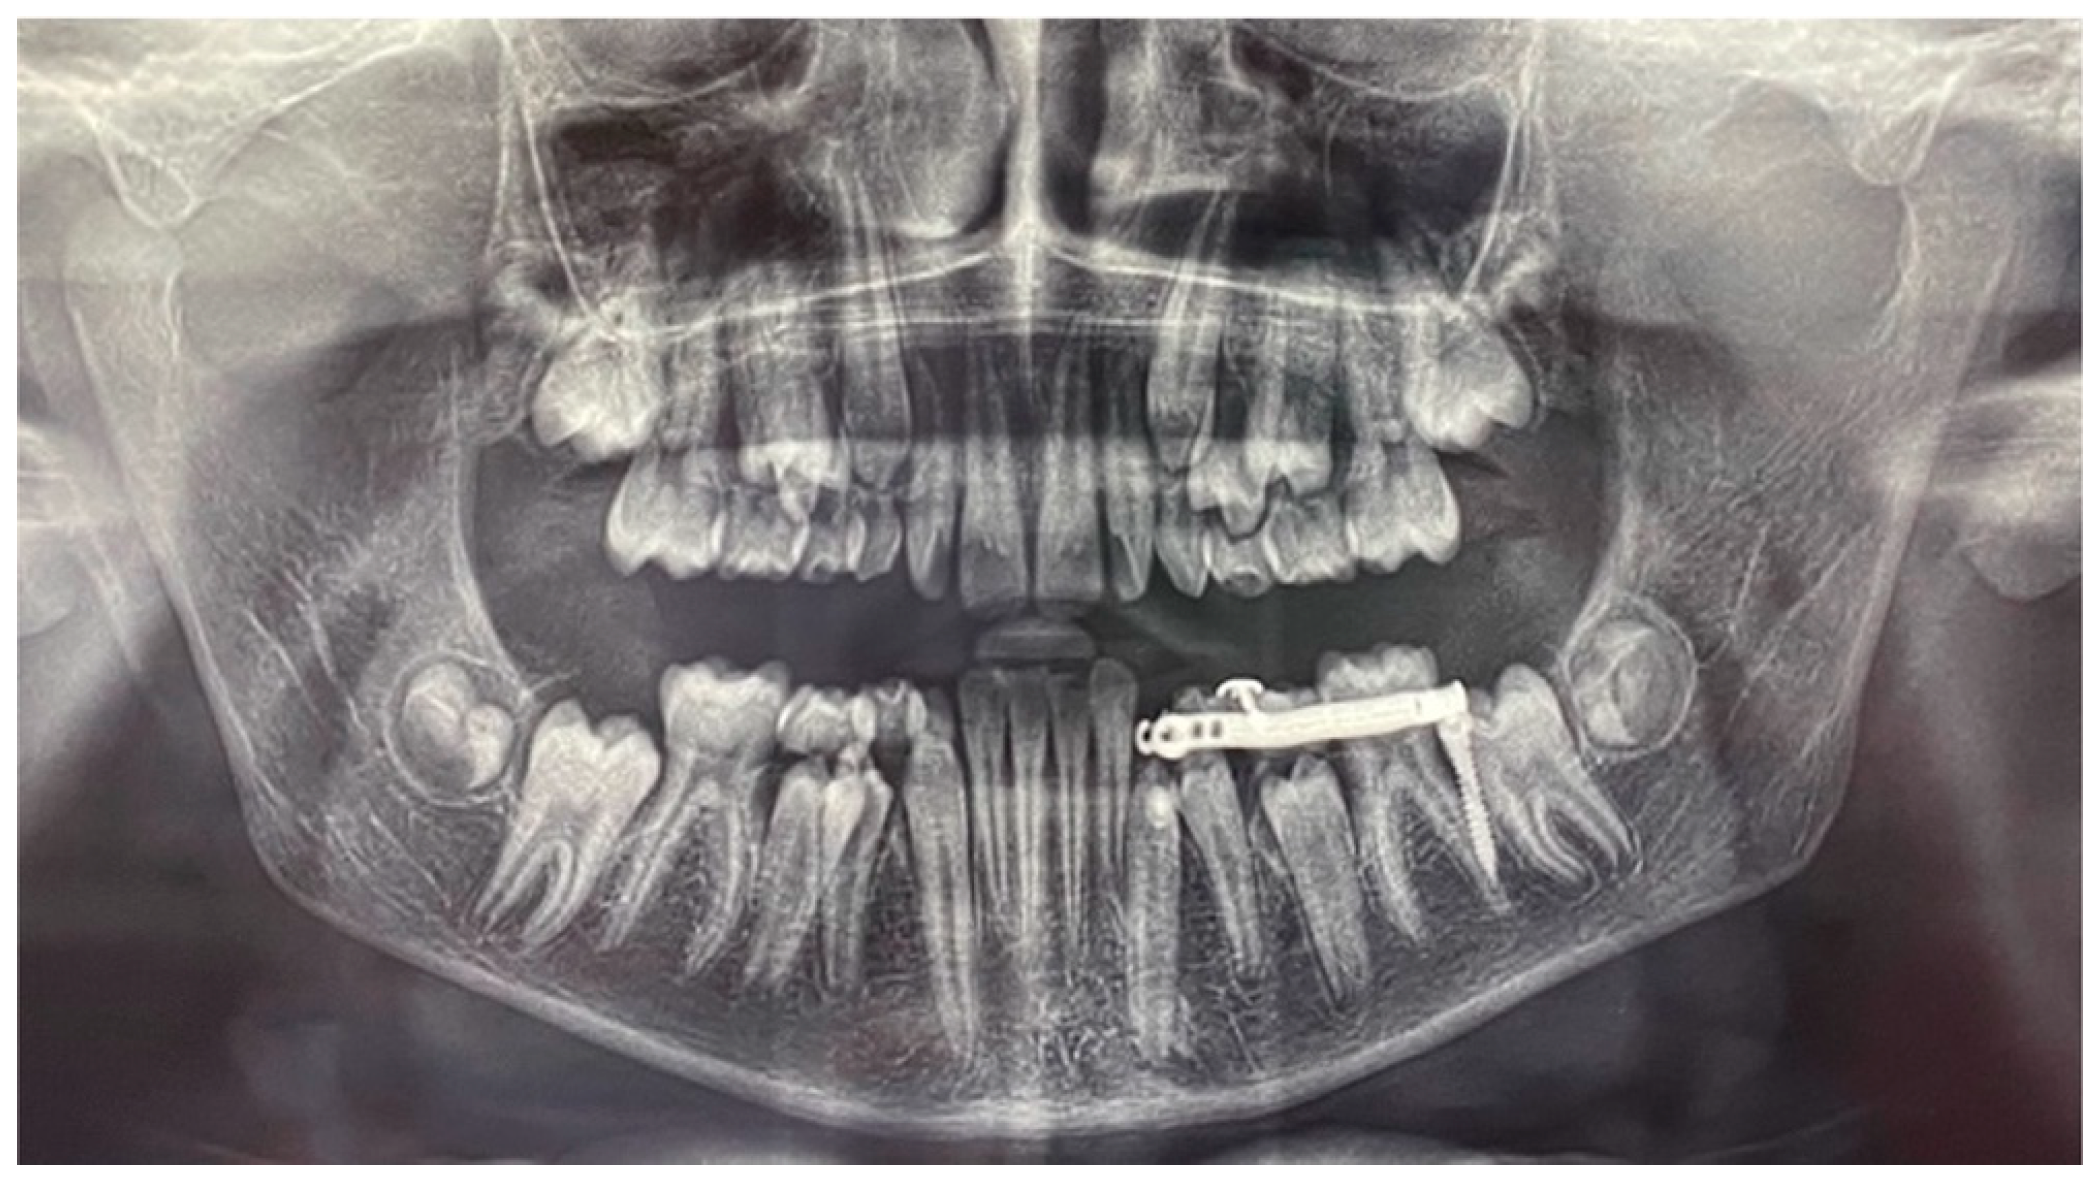

After 12 months, the mandibular canine (element 3.3) was disimpacted, in the axis with its eruptive path and with a correct eruption angle (Figure 13). The crown of the element was visible. The space present and the subject’s still-early mixed dentition was considered favourable to spontaneous eruption and the tooth was allowed to passively erupt. The disimpaction appliance was then removed and the miniscrew, still stable, was removed by unscrewing it.

The tooth element was followed over time through clinical monitoring every month and radiographic follow-up every 6 months (Figure 14).

Figure 12. Panoramic radiography of treatment progress (1 year after the first panoramic radiograph).

Figure 13. Panoramic radiograph at the end of the orthodontic traction with the customized skeletal anchorage device.